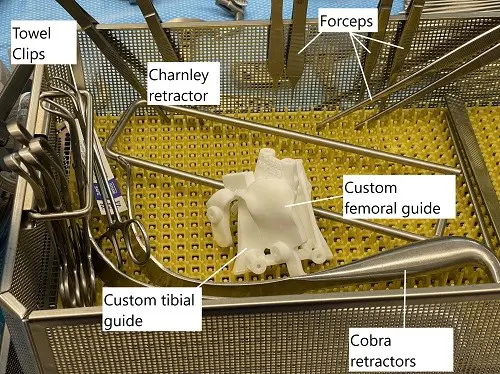

Intraoperative image showing custom cutting blocks.

The above intra-operative challenges may warrant additional bone cuts and may require additional sizes of the implants to fit the changed anatomy. Off-the-shelf implants come in various sizes that may fit the customized bone cuts.

Both customized cutting blocks and customized implants are aimed towards increasing the efficiency of the surgery and achieving better kinematic results of the surgery. While customized cutting blocks help in accurate cutting of the bone, the customized implants are designed according to the patient’s knee anatomy. Speak with your orthopedic surgeon what type of customized knee surgery is best suited in your case.